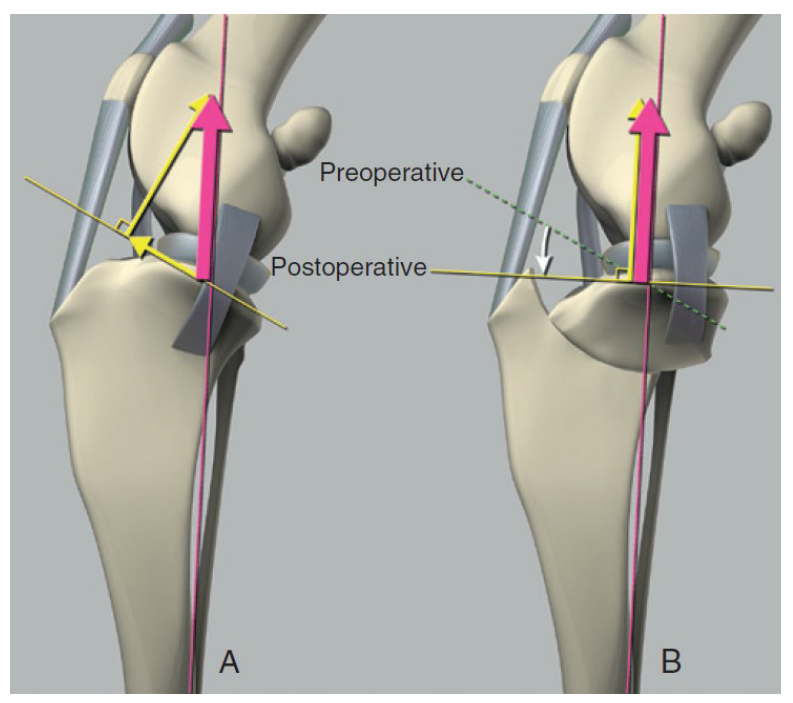

Analogy:

Pic 1 (normal joint): The rope (cranial cruciate ligament) is holding the red car 🚗 (Femur) and preventing it from sliding down the slope⛰ (Tibia).